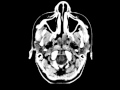

Nasal Polyposis

These images demonstrate two large polypoid soft tissue masses arising from the posterior nasal cavity and extending to nasopharynx. There is no central enhancement or adjacent osseous destruction. The masses narrow the nasopharynx. Findings are compatible with nasal polyposis. In addition, the palatine tonsils are slightly enlarged which may be age-related as this is a relatively young patient. This patient presented with a history of nasal stuffiness. Common presenting symptoms of nasal polyposis include nasal stuffiness, headache, facial pain, rhinorrhea. The etiology is believed to be a result of chronic inflammation and is associated with asthma, aspirin sensitivity/intolerance, and cystic fibrosis. The polyps may be of mucoid or soft tissue density. They may cause bony remodeling, sinus trabeculae attenuation, or truncation of the bony middle turbinate. Medical treatment is first line and consists of steroids. Surgery is reserved for symptomatic patients or extra-sinonasal involvement. This patient eventually went on to surgery.